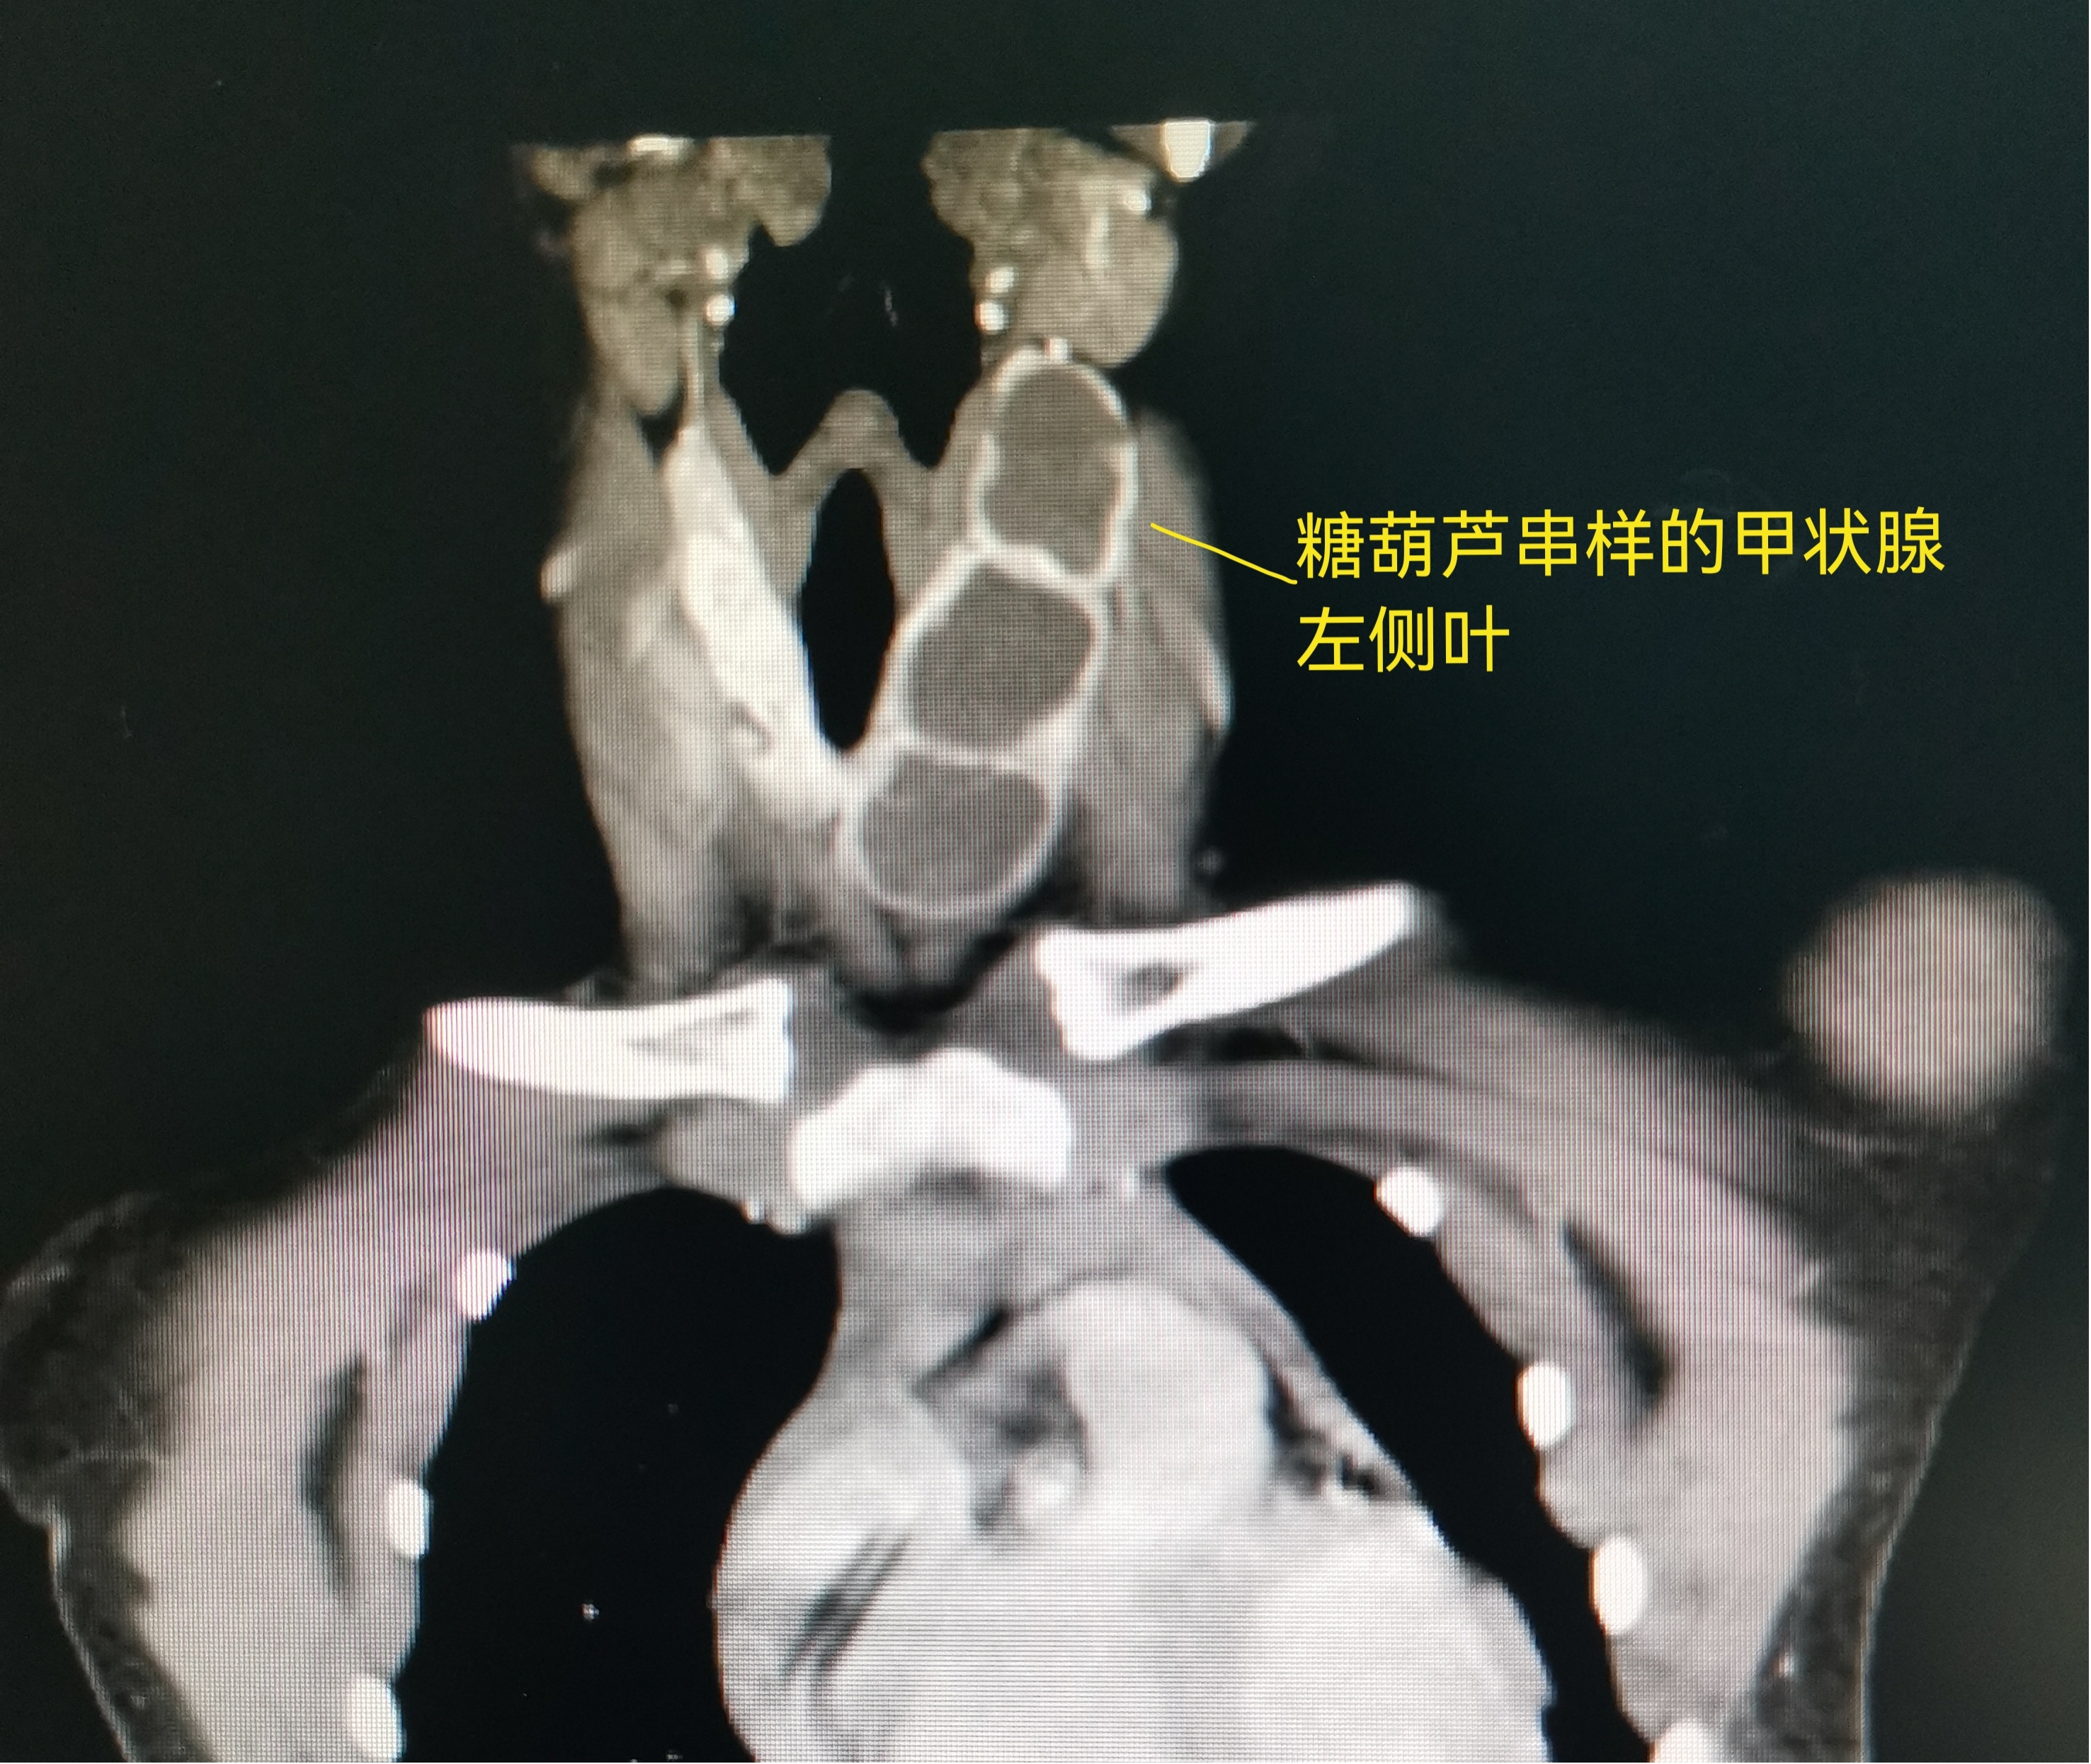

科室主任王慧玲及科室特聘专家张超杰主任在知道轩轩妈妈的顾虑后,对小轩的情况进行了讨论,CT结果显示小轩的甲状腺肿物比较大,而且呈糖葫芦串样,从甲状腺上极逐个排列直至甲状腺下极,上极的位置比较高,靠近下颌下腺,手术是肯定要做的,如果常规开放手术切除,做小切口,会因为上极位置高,容易损伤周围的血管神经,如果做大切口,颈部的疤痕会很明显,随着生长发育,疤痕牵扯,有可能会影响颈部的活动;选择腔镜,切口可以隐藏,但是对于主刀医生来说,难度会大很多。经过张超杰主任、王慧玲主任联合手术室及麻醉科的专家反复多次研究、探讨,最后为小轩制定了腔镜手术的方案。